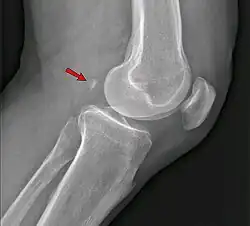

In der Betrachtung von seitlichen Röntgenaufnahmen des Kniegelenkes steht oft die Frage eines traumatisch abgesprengten Knochenfragmentes im Raum. Die Fabella weist jedoch, im Gegensatz zu einem Fragment, eine allseitige Kortikalis ohne Kontinuitätsunterbrechung auf und ist als Normvariante anzusehen.